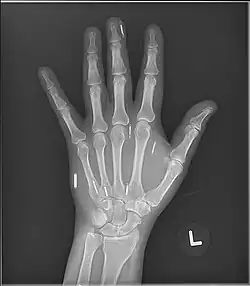

Other medical imaging technologies like X-ray and CT scanners do not pose a similar risk. Rather, X-rays can be used to locate implants.